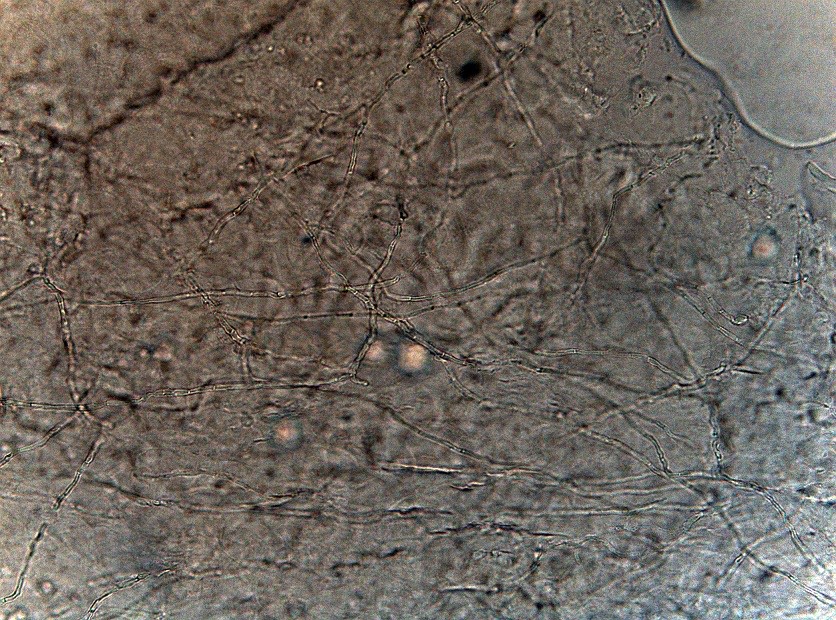

2053. При микроскопии соскоба с ногтевой пластины выявлена микроскопическая картина, соответствующая инфекции